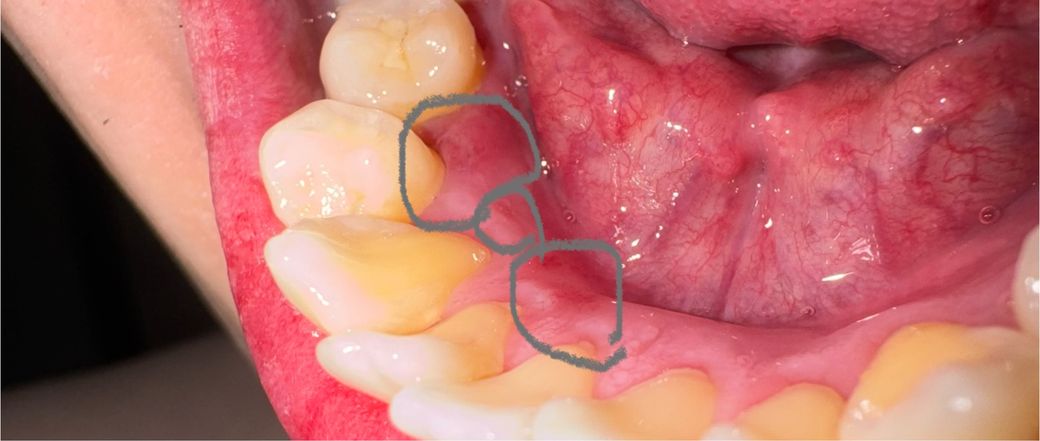

아래치아 안쪽 잇몸에 상처(까짐이)여러개 생겼는데 봐주세요

아침에 치아를 보는데 아래쪽치아 안쪽 잇몸

사진속 동그라미 부분쪽에 옅은상처(까짐)이 여러개

생겼는데요 물이나 음식부분이 닿으면 살짝 통증도

있는데 왜그런걸까요? 집에 오라메디 있는데

오라메디 바르면 될까요?

아니면 치과를 가봐야될까요?

• 1번 째 사진